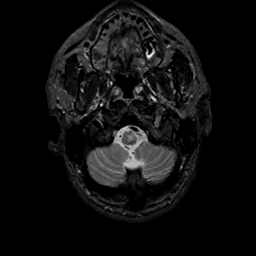

MR Study #11, May 5, 1991 -- Slice #4

[Home][Help][Clinical][Tour 1][Tour 2] Slice 4